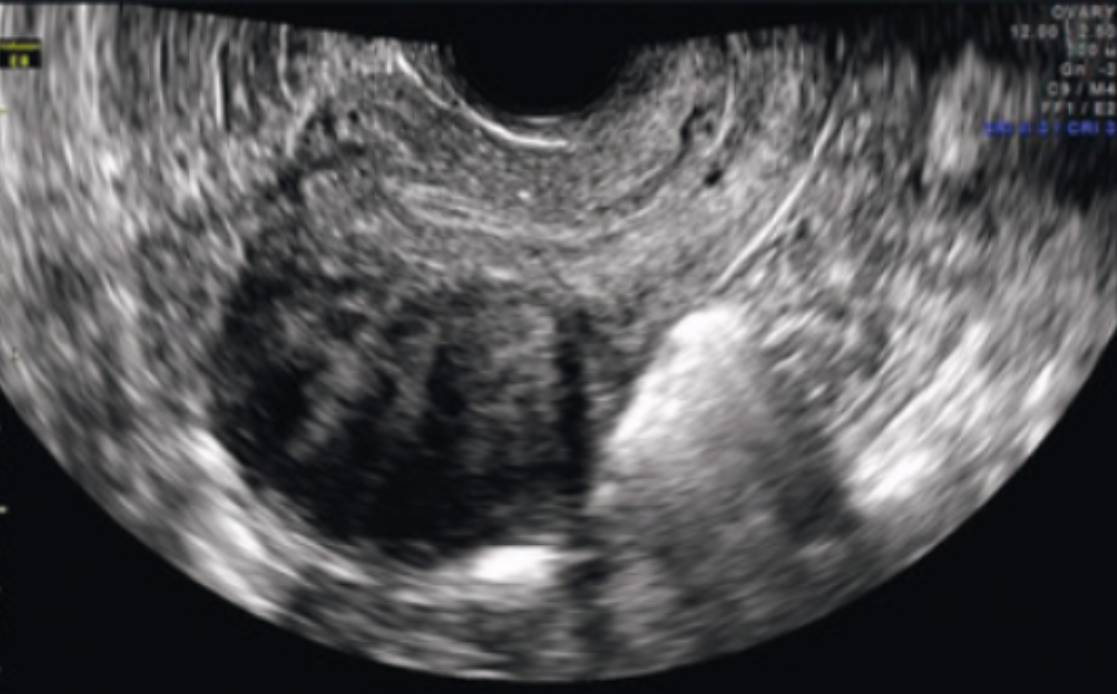

What type of fibroid is depicted in this image?

a. Intramural

b. Submucosal

c. Subserosal

d. Pedunculated

Subserosal

Where is this fibroid located in the uterus?

a. Anterior

b. Posterior

c. Cervical

d. Fundal

Anterior

Is this image endovaginal or transabdominal?

a. Endovaginal

b. Transabdominal

Endovaginal